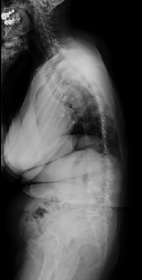

他、側弯変形は必ず大なり小なりの回旋変形を伴います。脊柱の回旋変形は胸郭(肋骨)の回旋につながり、これにより側弯の患者さんは背中の片方が出っ張っています(多くは右)。リブハンプと言いますが、脊柱変形矯正によりこの回旋変形も改善します。この症例も術前に肋骨がかなり隆起していますが、術後にこの隆起がかなり減じているのが分かります。(赤矢印)

この症例についても、横から見ると術前に右の背中が肋骨隆起(リブハンプ)により出っ張っています。(赤色矢印)

手術により側弯だけでなく回旋矯正、生理的胸椎後弯形成が成され、術後は右の背中の出っ張りがなくなり生理的な背中全体の丸みが復元されているのが分かります。(赤色矢印)